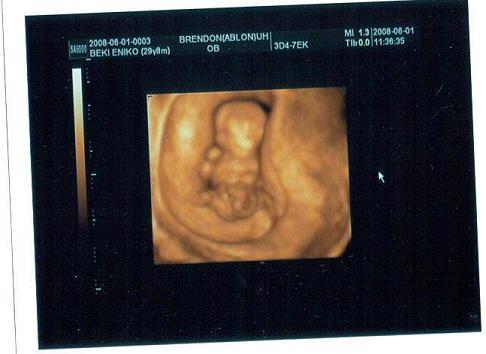

És a terhességem koránál nekem viszont egy héttel le van maradva a baba méretileg,de tudjátok én vagyok az a különc,aki nem a középidőben,hanem jóval később esett teherbe.